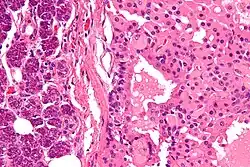

![]() Oncocitoma que afecta a la glándula parótida. | ||

Oncocitoma de parótida

Es poco frecuente, representa únicamente el 1% de los tumores que afectan a la glándula parótida. Se presenta como una masa no dolorosa superficial que muy raramente provoca metástasis. Es más habitual en la sexta década de la vida y el tratamiento de elección es la extirpación de la parótida.[6]